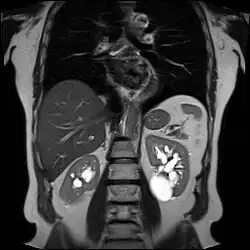

Numerous renal cysts are seen in the cystic kidney diseases, which include polycystic kidney disease and medullary sponge kidney.

Advanced polycystic kidney disease with multiple cysts.[13]